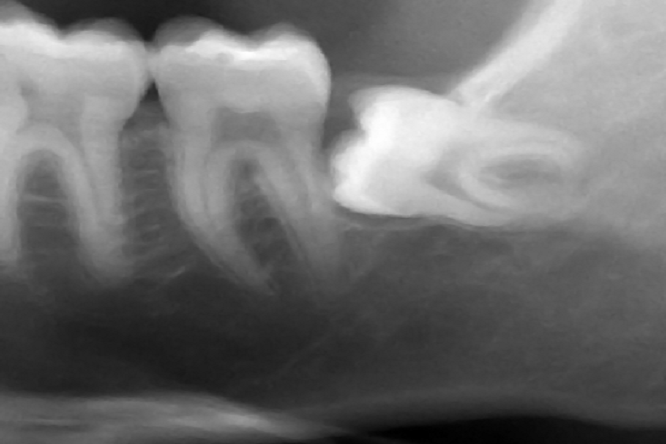

nhổ răng khôn mọc lệch 90 độ

Nhổ răng khôn mọc lệch 90 độ.